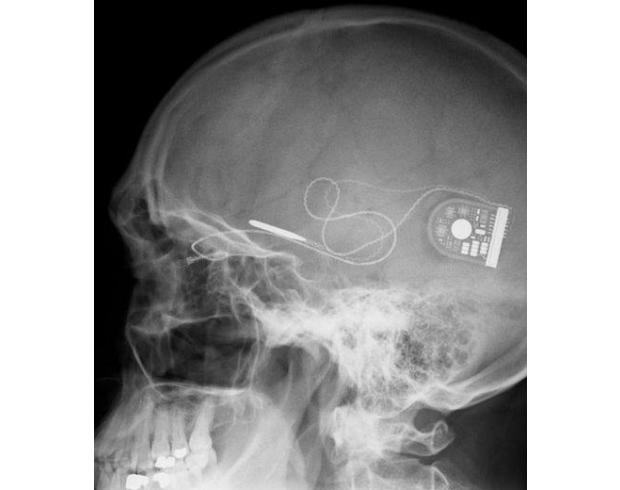

Un œil bionique restaure une partie de la vision à des aveugles : Un groupe de scientifiques allemands a mis au point un œil bionique capable de redonner la vision à des personnes aveugles. Le dispositif vient directement concurrencer le modèle américain qui vient tout juste de voir sa commercialisation autorisée. Les premiers essais sont très encourageants. L'oeil bionique est constitué d'une puce insérée au niveau de la rétine, d'un câble fin et d'un appareillage placé derrière l'oreille pour alimenter le tout Dormir Moins bête Walid